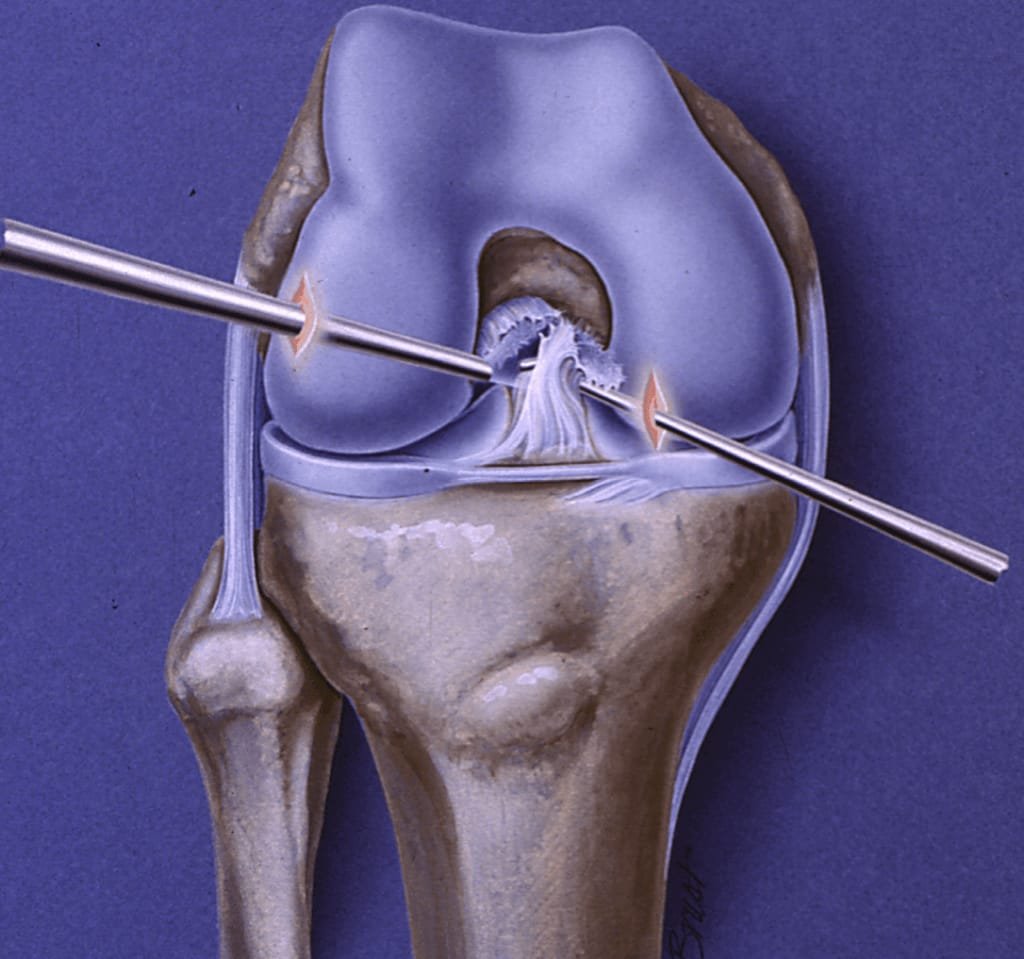

ACL surgery is performed to restore stability to the knee after a ligament tear, which often occurs during sports or sudden twisting movements. The damaged ligament is reconstructed using a graft, providing strength and stability needed for high-impact activities. Minimally invasive arthroscopic techniques allow for smaller incisions and faster recovery.

The choice of graft—whether from the patient’s own tissue or a donor—depends on lifestyle, activity level, and overall health. Modern surgical methods ensure precise placement of the graft, replicating the natural anatomy of the ACL. This significantly reduces the risk of reinjury and enhances long-term knee stability.